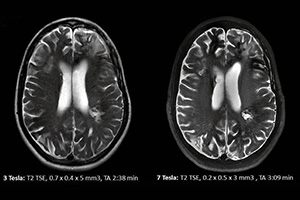

Компания Star-Test, предоставляющая диагностические услуги в Стамбуле с 1993 года, располагает самыми передовыми радиологическими устройствами с технологией.